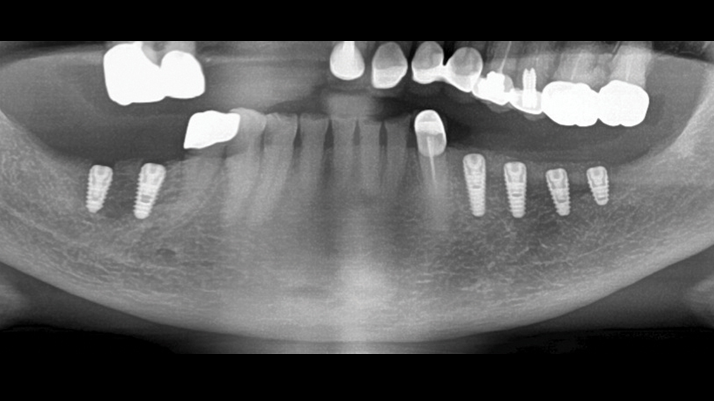

Clinical case: Installation of dental implants in complicated anatomic conditions using crest lifting methods

- Courtesy of Dr.Alexander Lysov, Russia -

AnyRidge, complicated anatomic conditions, crest lift, MICA Kit, Dr. Alexander Lysov, bone regeneration, GBR, #26, maxillary posterior

AnyRidge implant system, MICA Kit